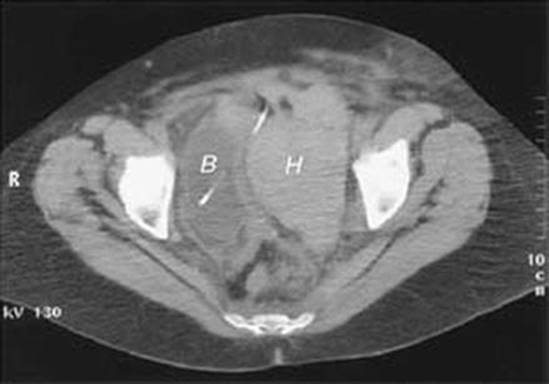

If a patient has pain and swelling consistent with retropubic hematoma, obtain a complete blood count and coagulation studies. In patients who are hemodynamically stable but with ongoing pain and distention, an ultrasound may be obtained to visualize a retropubic hematoma, either transabdominally or transvaginally (Fig. 19.2). Alternatively, a CT scan of the pelvic with IV contrast can be obtained (Fig. 19.3); extravasation of contrast may be identified in the retropubic space.

Fig. 19.3

Pelvic computed tomography scan of patient with a 10-cm hematoma (H) in the space of Retzius next to the bladder (B) (Walters et al. [24], with permission of the American College of Obstetricians and Gynecologists)